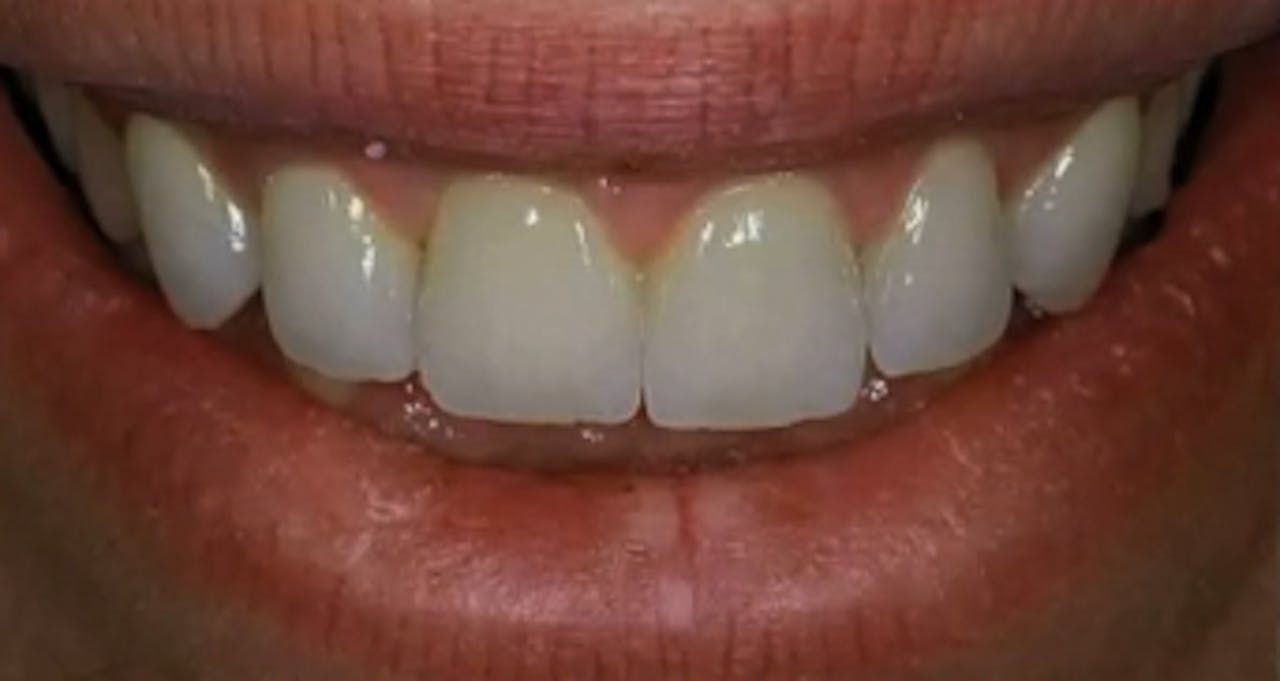

Before / After GIDE Dental Implant Center Gide Dental Reviews Gide dental institute, los angeles, california. 31,762 likes · 74 talking about this · 887 were. Find reviews, ratings, directions, business hours, and book appointments online. Dive deep (at your own pace) in a comprehensive online master class or residency with topics covering implant dentistry, esthetic dentistry,. • 550+ clinical videos on web and app • new dental videos added.. Gide Dental Reviews.

Before / After GIDE Dental Implant Center Gide Dental Reviews Premiere provider of online dental education. Learn from the world's most trusted faculty and advance your skills with gide. Find reviews, ratings, directions, business hours, and book appointments online. Clinical videos, expert interviews, live broadcasts over. Gide dental | 280 followers on linkedin. • 550+ clinical videos on web and app • new dental videos added. Dive deep (at your. Gide Dental Reviews.